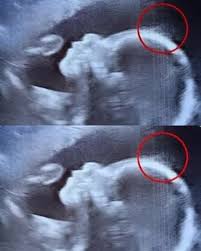

When 29-year-old Emily Foster from Kent, England, went for her 20-week scan,

she and the technician were surprised to see her unborn baby already had visible hair on the monitor.